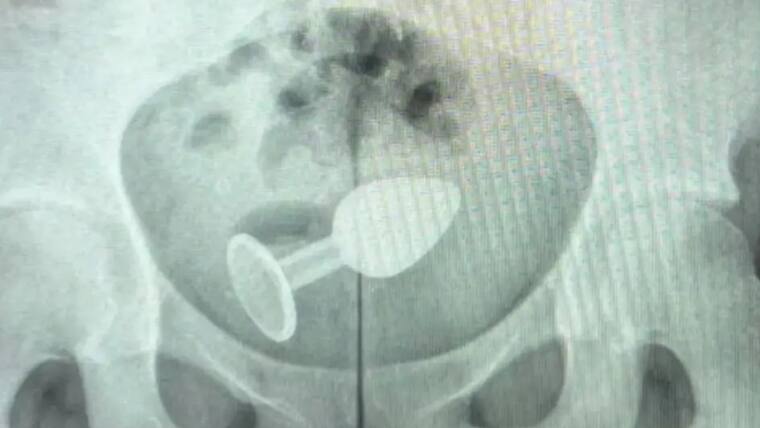

Realizó una radiografía y pudo evidenciar dónde se encontraba el plug, por lo que pudo ser atendida para retirarle el juguete.

Una mujer llegó a urgencias y tuvo que ser hospitalizada luego de experimentar con un ‘plug anal’ en el acto sexual, que le causó una grave lesión e incluso quedó dentro de su cuerpo.